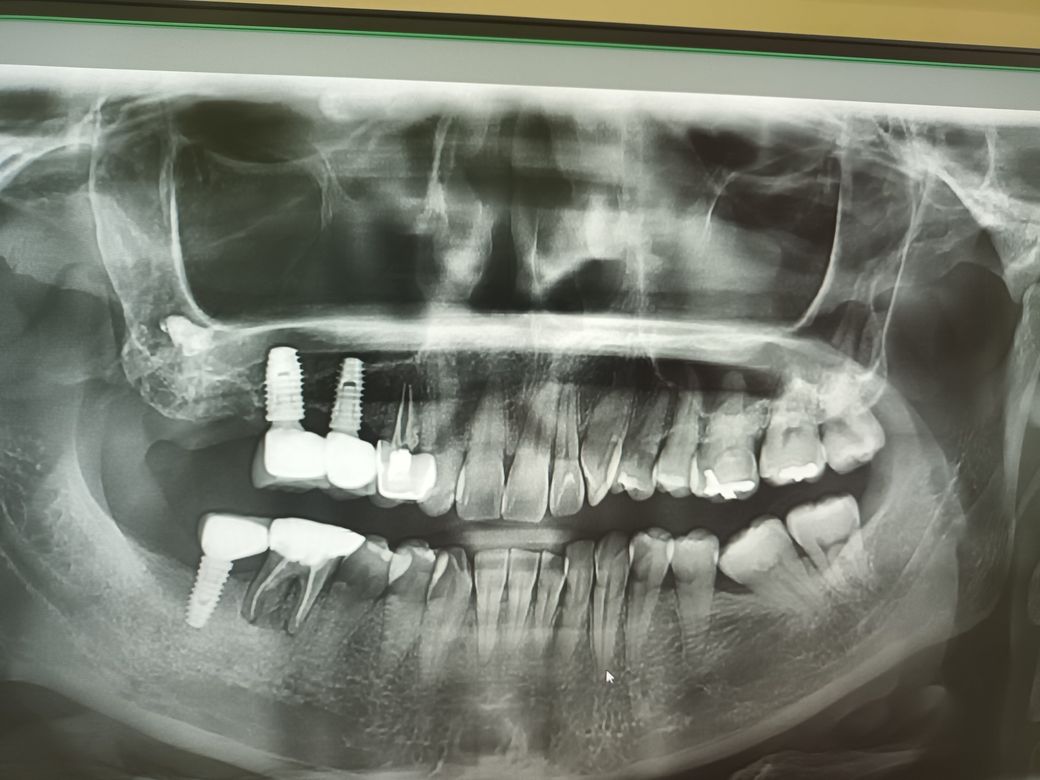

발치 후에도 잇몸쪽이 아픈데 왜그럴까요?

오른쪽 위어금니를 살리려고 노력하다 발치했는데 뺀부분 위쪽으로 욱신거리는 통증이 계속있고 두통도 동반되어 괴롭네요.

파라마 사진찍고 치과에서는 하얀부분이 뼈가 채워지고 있다고 하는데 계속 아파요

말씀하신 부분 쪽 x-ray 에서 하얗게 보이는 물질이 있습니다. 이것이 뼈이식 등으로 채워진 것인지, 치아 뿌리를 발치하고 남아 있는 잔존치근인지에 대한 판단이 필요합니다. 만약에 잔존 치근이 남아 있고 해당 부분이 상악동 안으로 들어가 있다면 이것을 제거하는 수술을 해야 합니다. 다만 지금으로서는 정확한 판단이 어려우므로 해당 치과가 아닌 다른 치과를 방문하여 x-ray 검사를 한 번 해보시길 바랍니다.